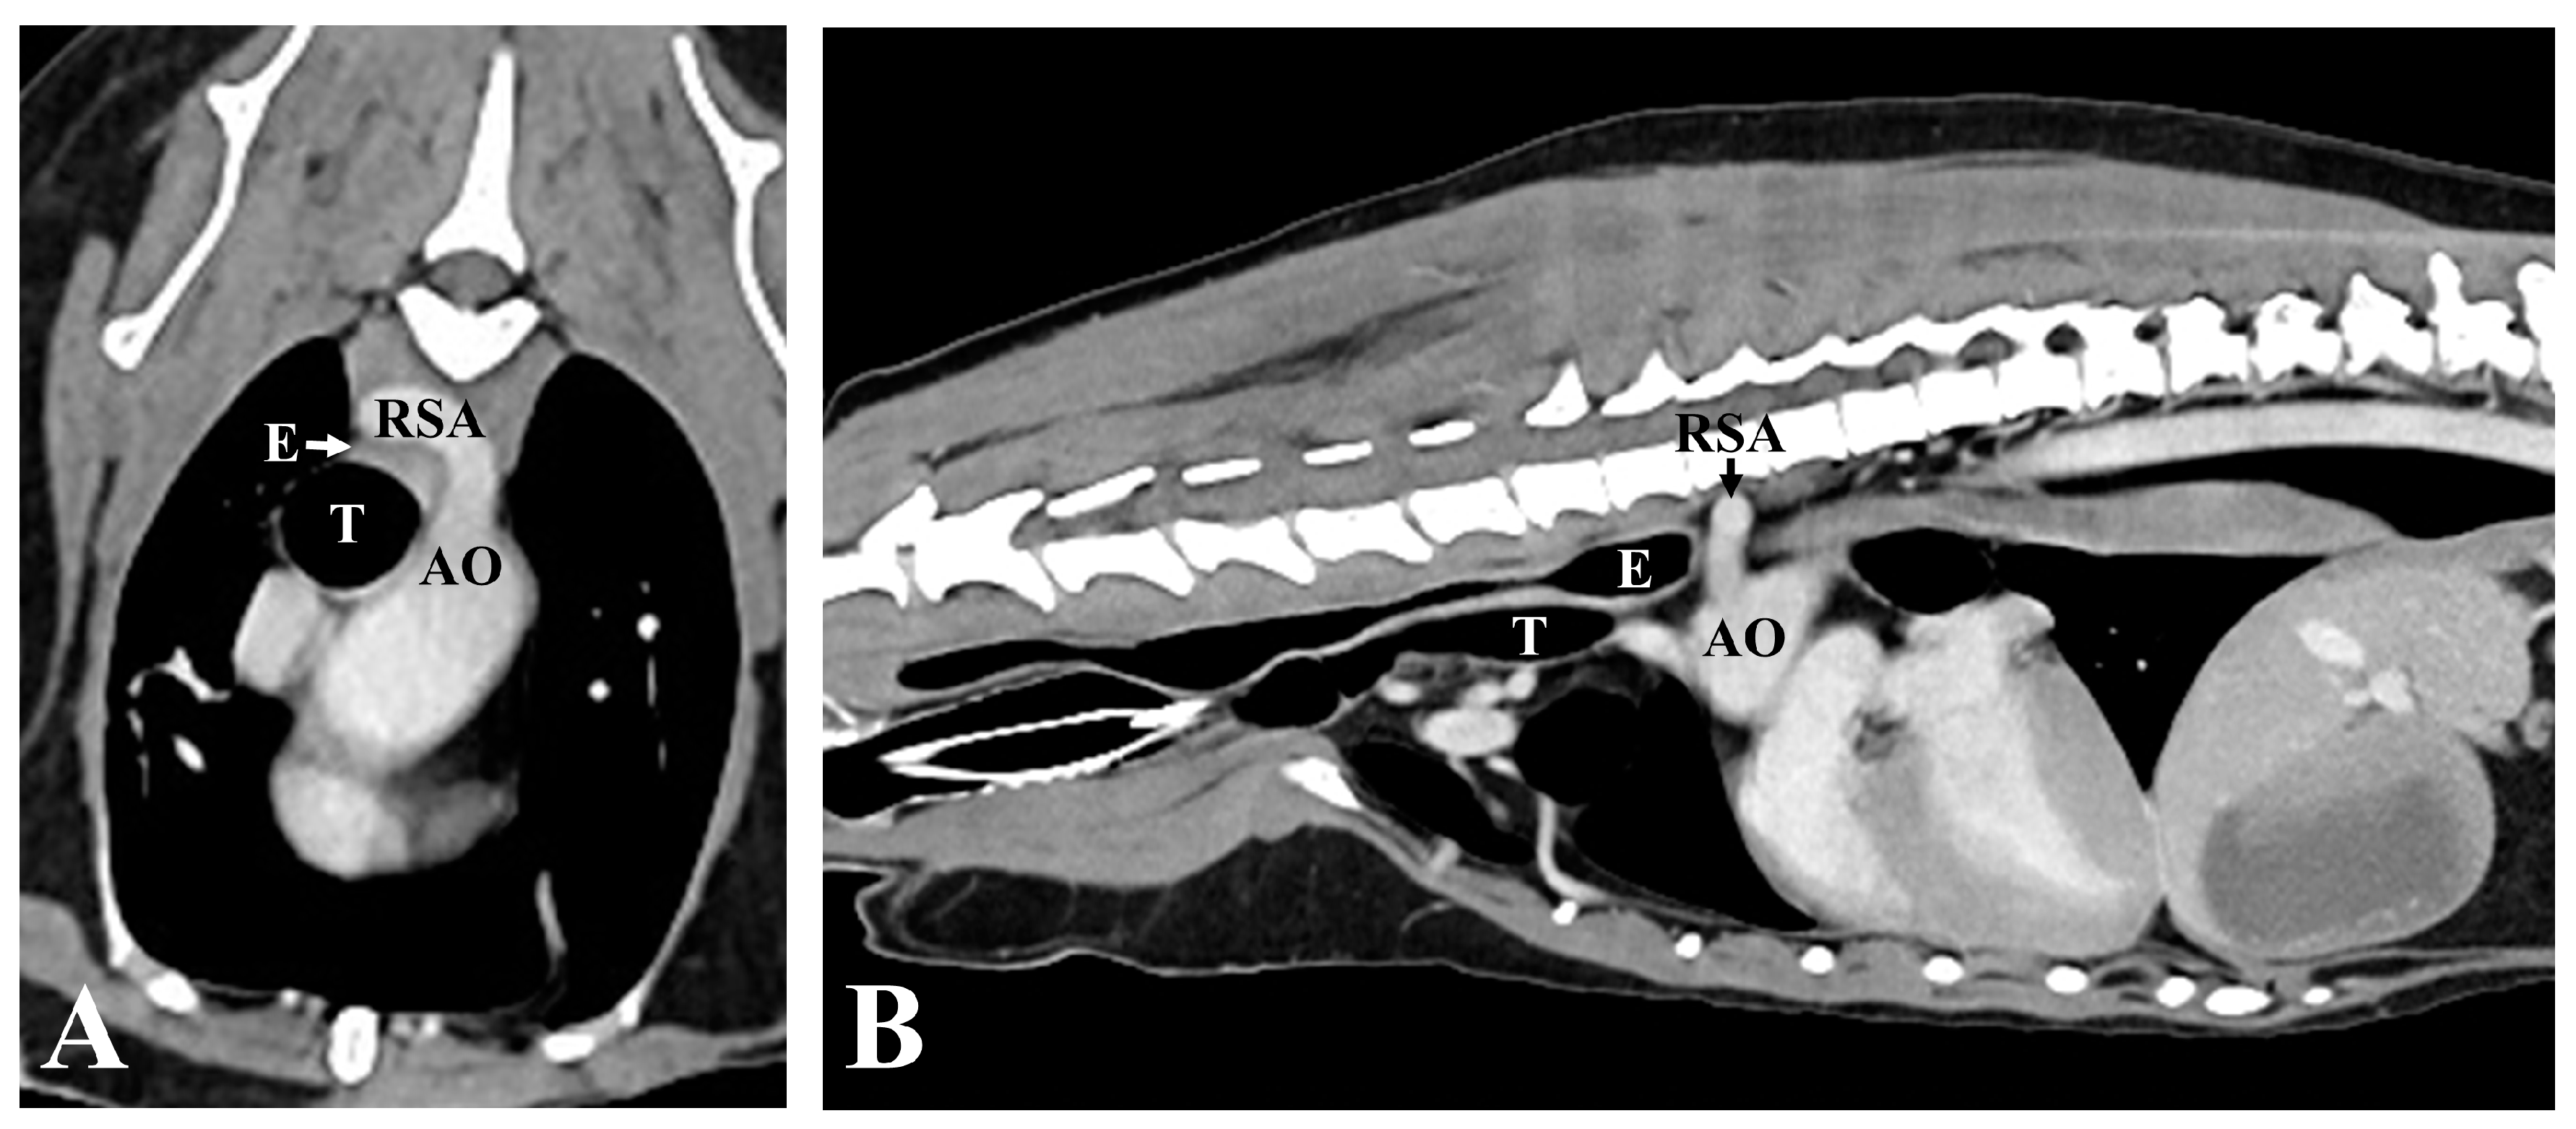

2. Case Description

3. Diagnostic Assessment, Intervention, and Outcomes